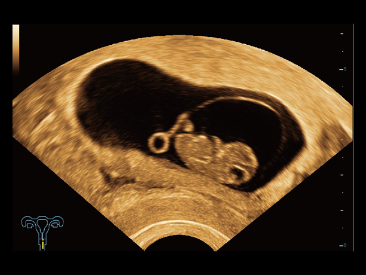

Naast de hoogwaardige beeldvormingskwaliteit verbetert de Resona 7 tevens de klinische onderzoeksmogelijkheden met de revolutionaire V Flow voor vasculaire hemodynamische evaluatie, en de intelligentste vlakacquisitie van een 3D-gegevenssets voor de diagnose van het foetale, centrale zenuwstelsel. Met zijn combinatie van de meest intu?tieve, op vingerbewegingen gebaseerde multi-aanrakingsbediening en alle essenti?le klinische functies loopt de Resona 7 voorop in de nieuwe golven van ultrasoundinnovatie.